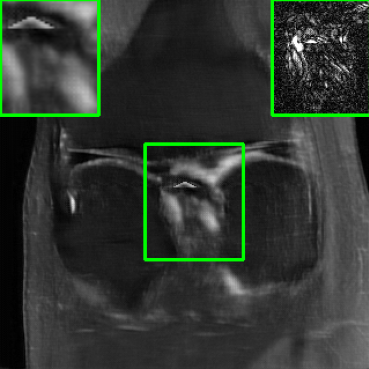

Performance on the Stanford FSE Dataset: We also performed image reconstructions with the Stanford multi-coil FSE dataset, which is a smaller dataset. We used same settings for the networks and training as in Section IV-A. Table III shows that LONDN-MRI significantly outperforms the globally learned MoDL network at both 4x and 8x acceleration. This indicates benefits for the proposed framework for smaller, more diverse datasets. Figs. 7 and 8 display visual comparisons that show the LONDN-MRI scheme recovering sharper features than the globally learned network.

| Ground Truth | Initial | Global | LONDN-MRI | LONDN-MRI | Oracle |

| (1 iteration) | (2 iterations) | ||||

![]() |

| PSNR = dB | PSNR = 19.41 dB | PSNR = 26.52 dB | PSNR = 27.76 dB | PSNR = 27.85 dB | PSNR = 27.92 dB |